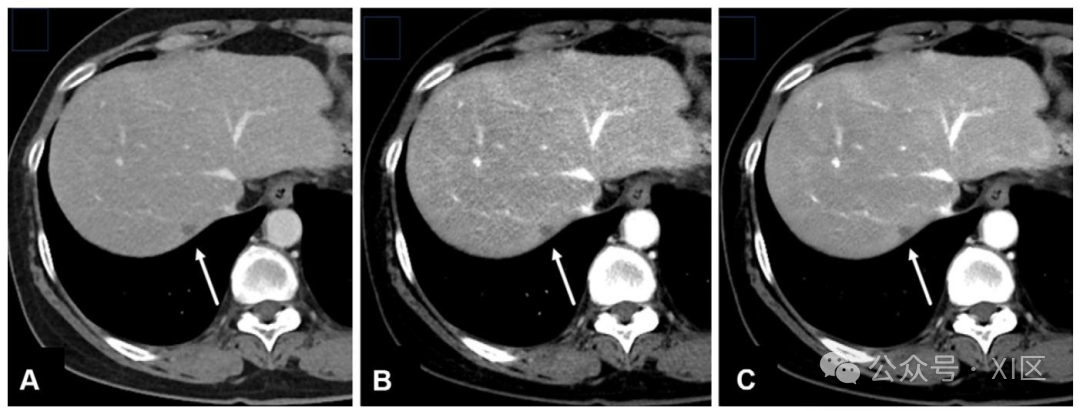

轴位增强 CT 图像显示一名研究参与者肝脏内的结直肠癌转移瘤(B 图箭头所示)。采用中等强度 TrueFidelity DLR 重建的图像(A 图),即使辐射剂量降低 66%,病变显影度仍略有提升,且与同一屏气状态下获取的标准剂量 FBP 图像(B 图)相比,该病变在标准剂量 FBP 图像中被阅片者遗漏,而在 DLR 图像中被成功识别。